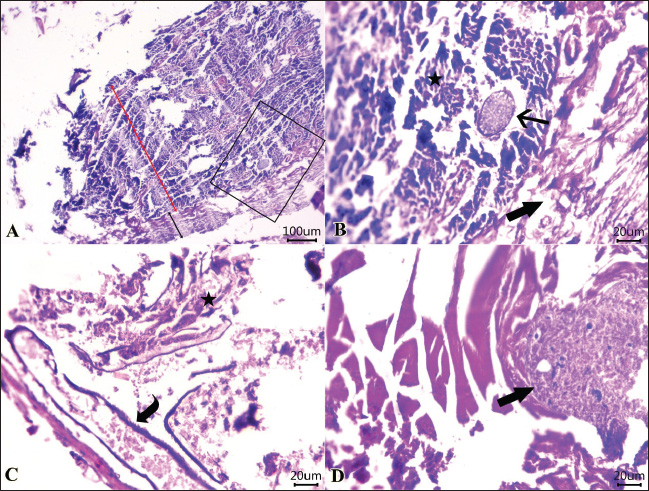

Examined sections from the intestine (Fig. 3) showed necrotic enteritis with the presence of rounded to ovoid-shaped structures “may be parasitic elements” in between necrotic and detached enterocytes. Moreover, extensive myonecrosis is observed at the muscular layer and congested vasculature. Sections from the intestine (Fig. 4) showed necrotic epithelial lining mucosa beside the vacuolated and necrotic muscular layer. “Oval-shaped protozoal element” were also embedded between the necrotic columnar mucosal epithelium. Furthermore, congestion and hemorrhages within the mucosal and submucosal layers, as well as myolysis within the musculosa, were also detected.

Fig. 3. Photomicrographs of H&E-stained sections of shrimp intestine showing: A, B, C, D: rounded to ovoid-shaped structures “may be parasitic elements” (arrow) between necrotic and detached enterocytes (star), extensive myonecrosis at the muscular layer (thick arrow), and congested vasculature (curved arrow). (Scale bar 100 μm, and high magnification, 20 μm).